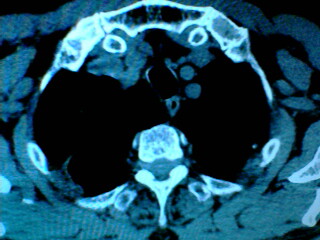

老年男性患者,右侧胸疼1月余(不是左侧),无其他症状

支持肺囊肿,液体含量多,可能与支气管不通.右侧胸膜局限性肥厚,可能是导致痛的原因.

支持肺囊肿,右侧胸膜肥厚粘连钙化.